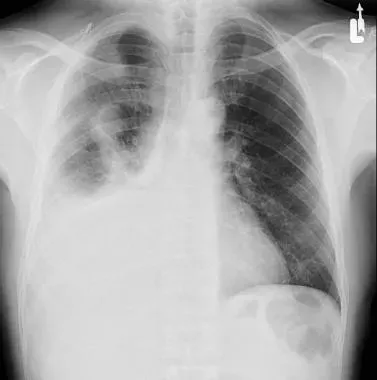

2단계, 흉부 X선 촬영입니다.

서서 찍은 단순 X선에서 보통 250mL 이상 흉수가 고이면 갈비뼈와 횡격막이 만나는 부분이 희미해지거나, 반달 모양의 음영이 보이기 시작한다고 알려져 있습니다.:contentReference[oaicite:21]{index=21}